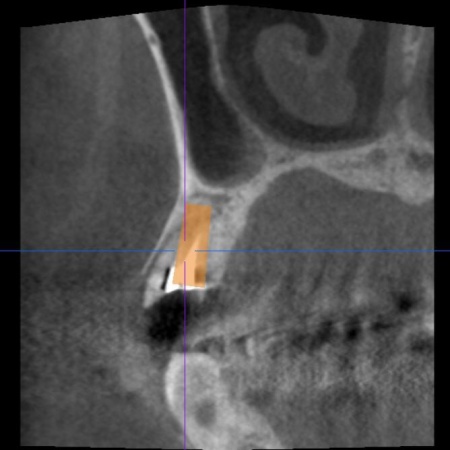

続いてインプラント手術を実施し、インプラントを正しい位置と角度で顎の骨に埋め込みました。

インプラント手術後は経過観察を行い、インプラントが顎の骨に結合したことを確認したら、インプラント上部に取り付ける人工歯を作製するために精密な型取りを実施します。